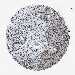

UROTHELIAL CANCER - Protein expressioni

A mouse-over function shows sample information and annotation data. Click on an image to view it in a full screen mode. Samples can be filtered based on level of antibody staining by selecting one or several of the following categories: high, medium, low and not detected. The assay and annotation is described here.

Note that samples used for immunohistochemistry by the Human Protein Atlas do not correspond to samples in the TCGA dataset.

Antibody stainingi

Antibody staining in the annotated cell types in the current human tissue is reported as not detected, low, medium, or high, based on conventional immunohistochemistry profiling in selected tissues. This score is based on the combination of the staining intensity and fraction of stained cells.

Each image is clickable and will lead to virtual microscopy that enables deeper exploration of all samples and also displays staining intensity scores, fraction scores and subcellular localization as well as patient and tissue information for each sample.

Antibody CAB018364

Staining

High

Medium

Low

Not detected

Intensity

Strong

Moderate

Weak

Negative

Quantity

>75%

75%-25%

<25%

None

Location

Nuclear

Cytoplasmic/membranous

Cytoplasmic/membranous,nuclear

Urothelial carcinoma, Low grade

Urothelial carcinoma, High grade